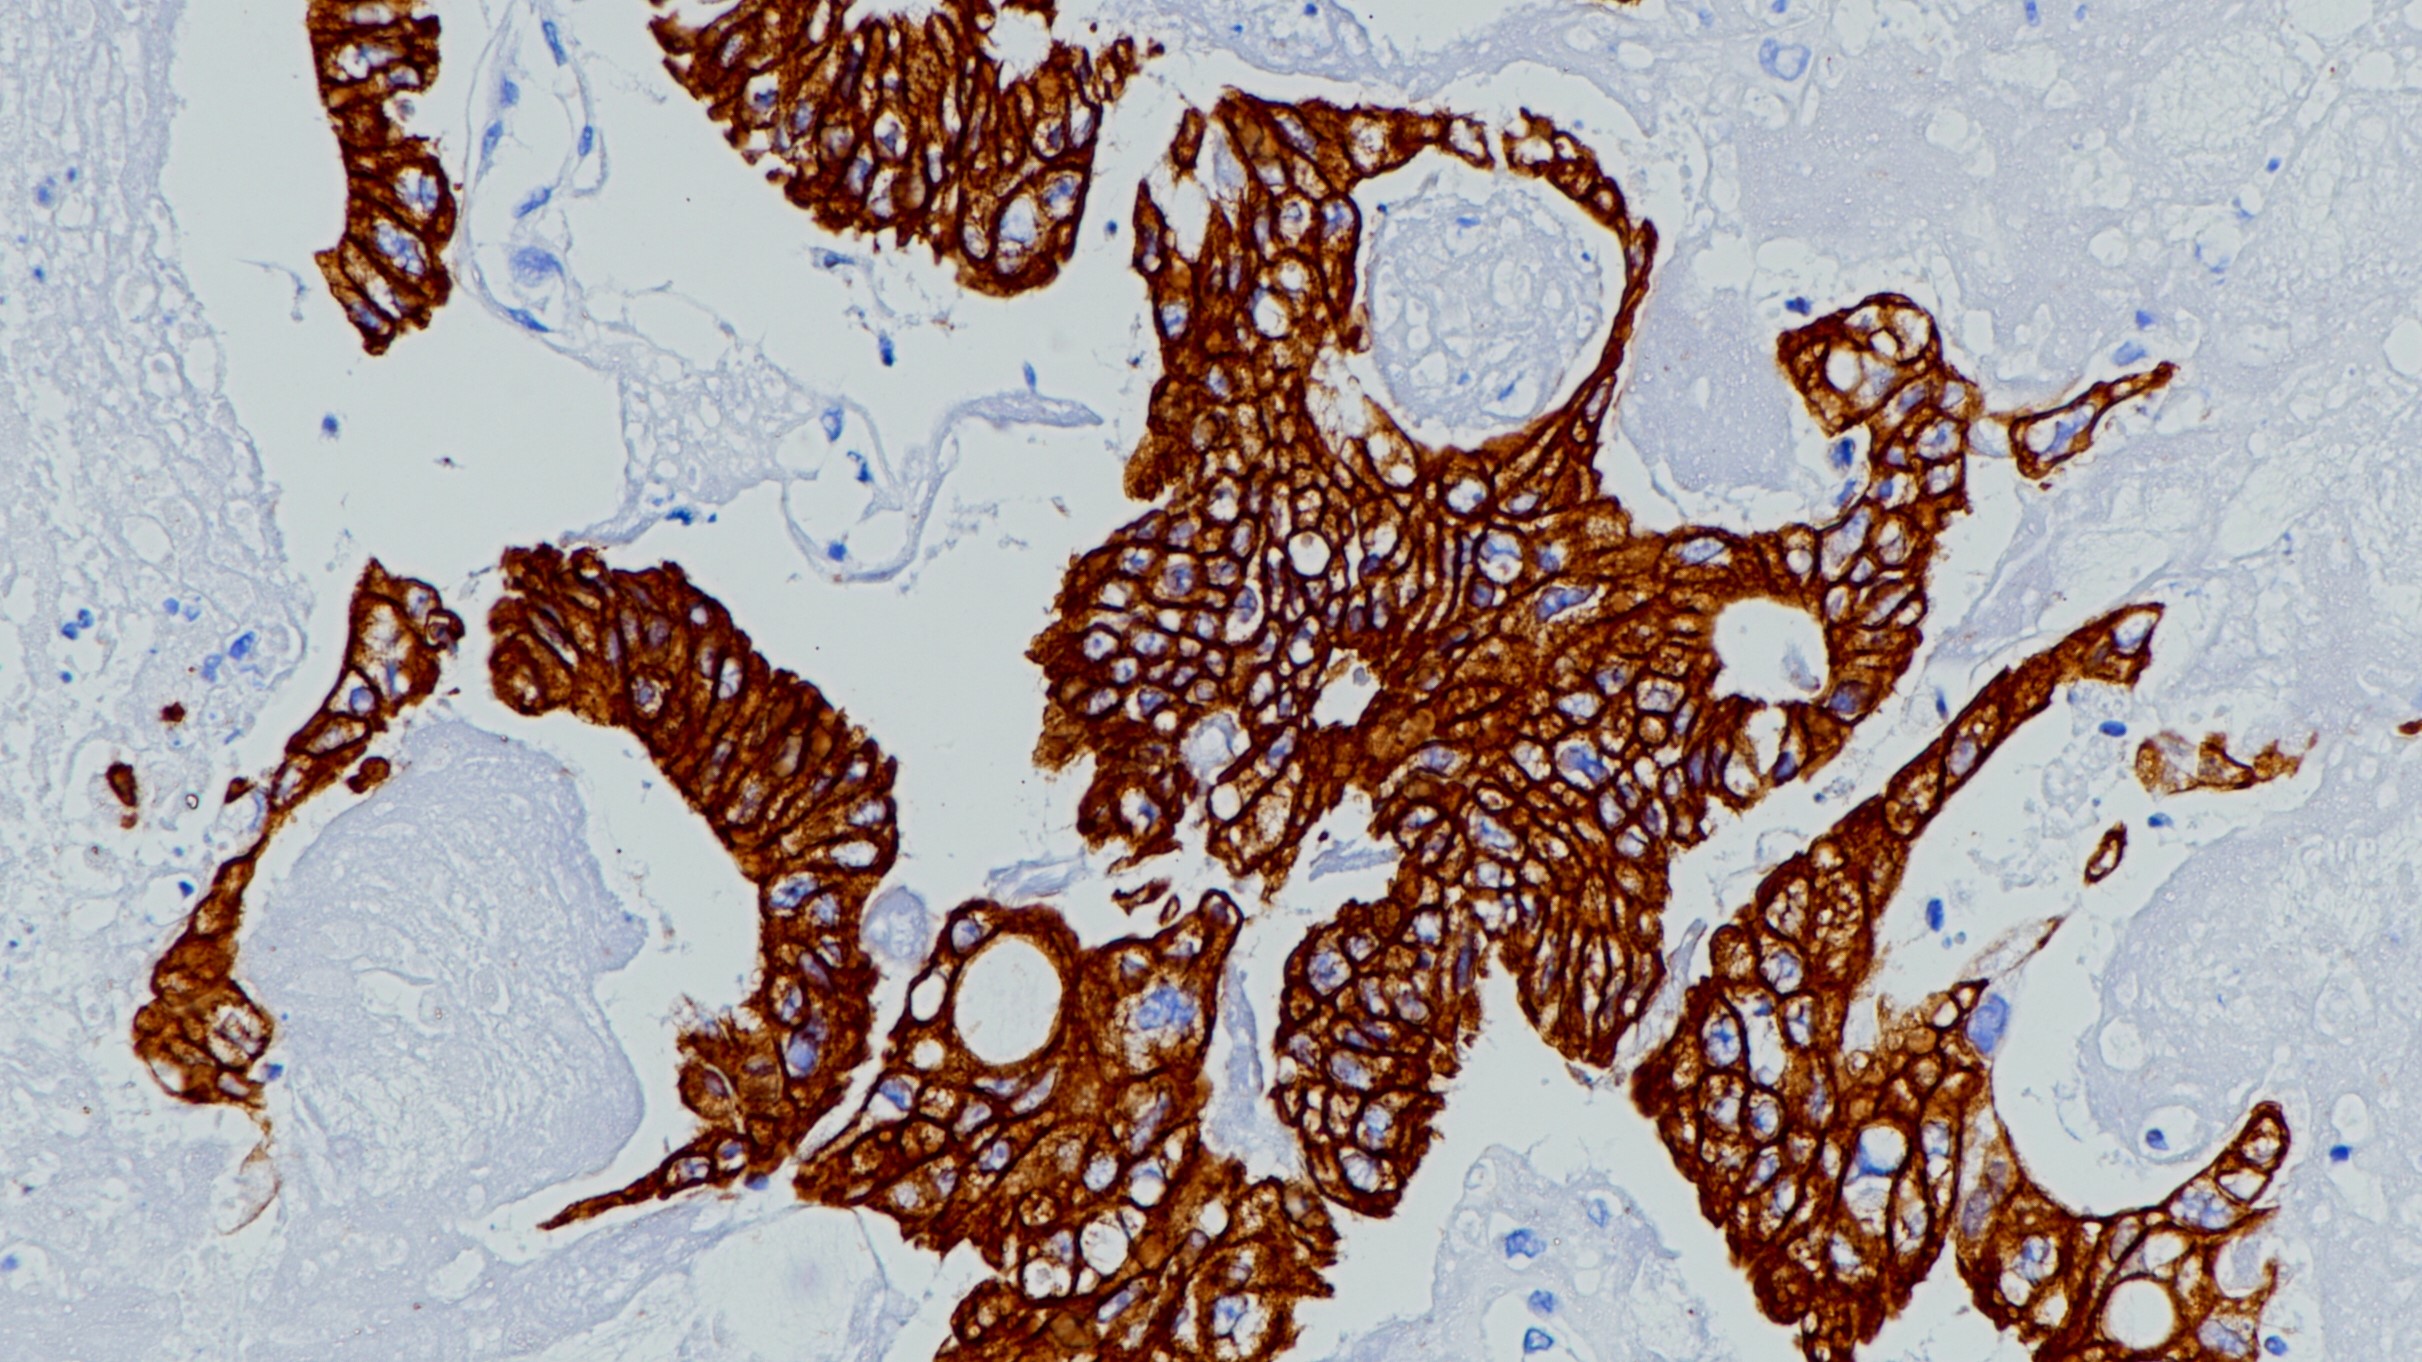

胰高血糖素在葡萄糖代谢和体内平衡中起着关键作用。胰高血糖素通过增加糖异生和减少糖酵解来调节血糖。胰高血糖素是胰岛素的一种反调节激素,在胰岛素诱导的低血糖状态下升高血糖水平。它在糖尿病的启动和维持高血糖状态中起着重要作用。胰高血糖素在胰岛的A细胞和整个胃肠道的L细胞中分泌。胰高血糖素检测胰高血糖素分泌细胞和肿瘤,如胰高血糖素肿瘤。

阳性对照

胰腺